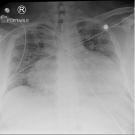

A 20-year-old man presented to the emergency department with a 3- to 4-week history of worsening dyspnea upon exertion, lower extremity edema, weakness, anorexia, and vomiting.